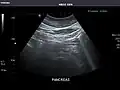

Pancreas -